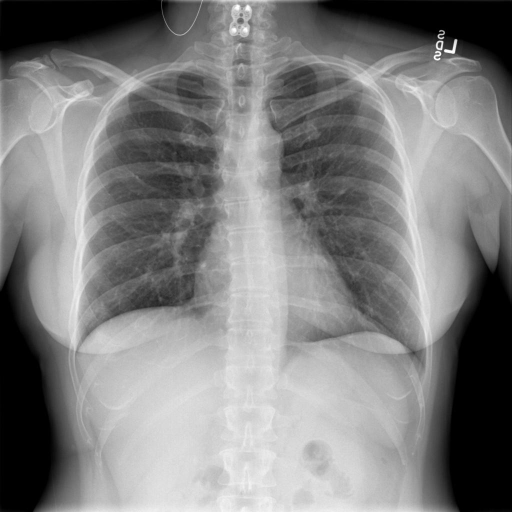

Indiana Dataset [19]: Set consists of 7284 CXRs, both frontal and lateral images with disease annotations, such as cardiomegaly, pulmonary edema, opacity or pleural effusion. Indiana Set is collected from various hospitals affiliated with the Indiana University School of Medicine. The set is publicly available through Open-i SM, which is a multimodal (image + text) biomedical literature search engine developed by U.S. National Library of Medicine. A typical example of a normal CXR (left) and a CXR with cardiomegaly abnormality (right) is shown in Fig. 1. Visually, it can be observed that the heart in the cardiomegaly example is quite big compared to that of the normal CXR.

Figure 1: An example of Normal CXR (left) and an example of a cardiomegaly CXR (right) from Indiana dataset. The pathology in the right CXR can be easily distinguished from the abnormal size and shape of the heart. -